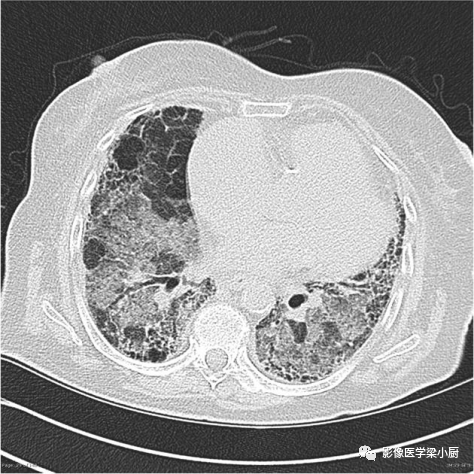

3.蜂窝:呈镞状囊性低密度影,囊壁光整,厚度1~3mm,直径常为3~10mm,偶尔可达2.5cm。蜂窝是HRCT的UIP型最具特征性的表现,蜂窝影预测UIP的灵敏度和特异度较高。

蜂窝的组成目前尚不清楚,推测为扩张的小气道,是纤维化进展的标志,提示预后差。

双肺呈弥漫蜂窝状改变